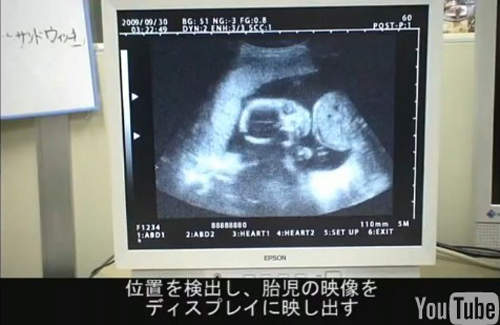

▼還可以用條碼讀取目前胎兒在肚子裡的樣子。

▼即使沒有懷孕,但看到這個超音波影像還是會莫名感動(!?)